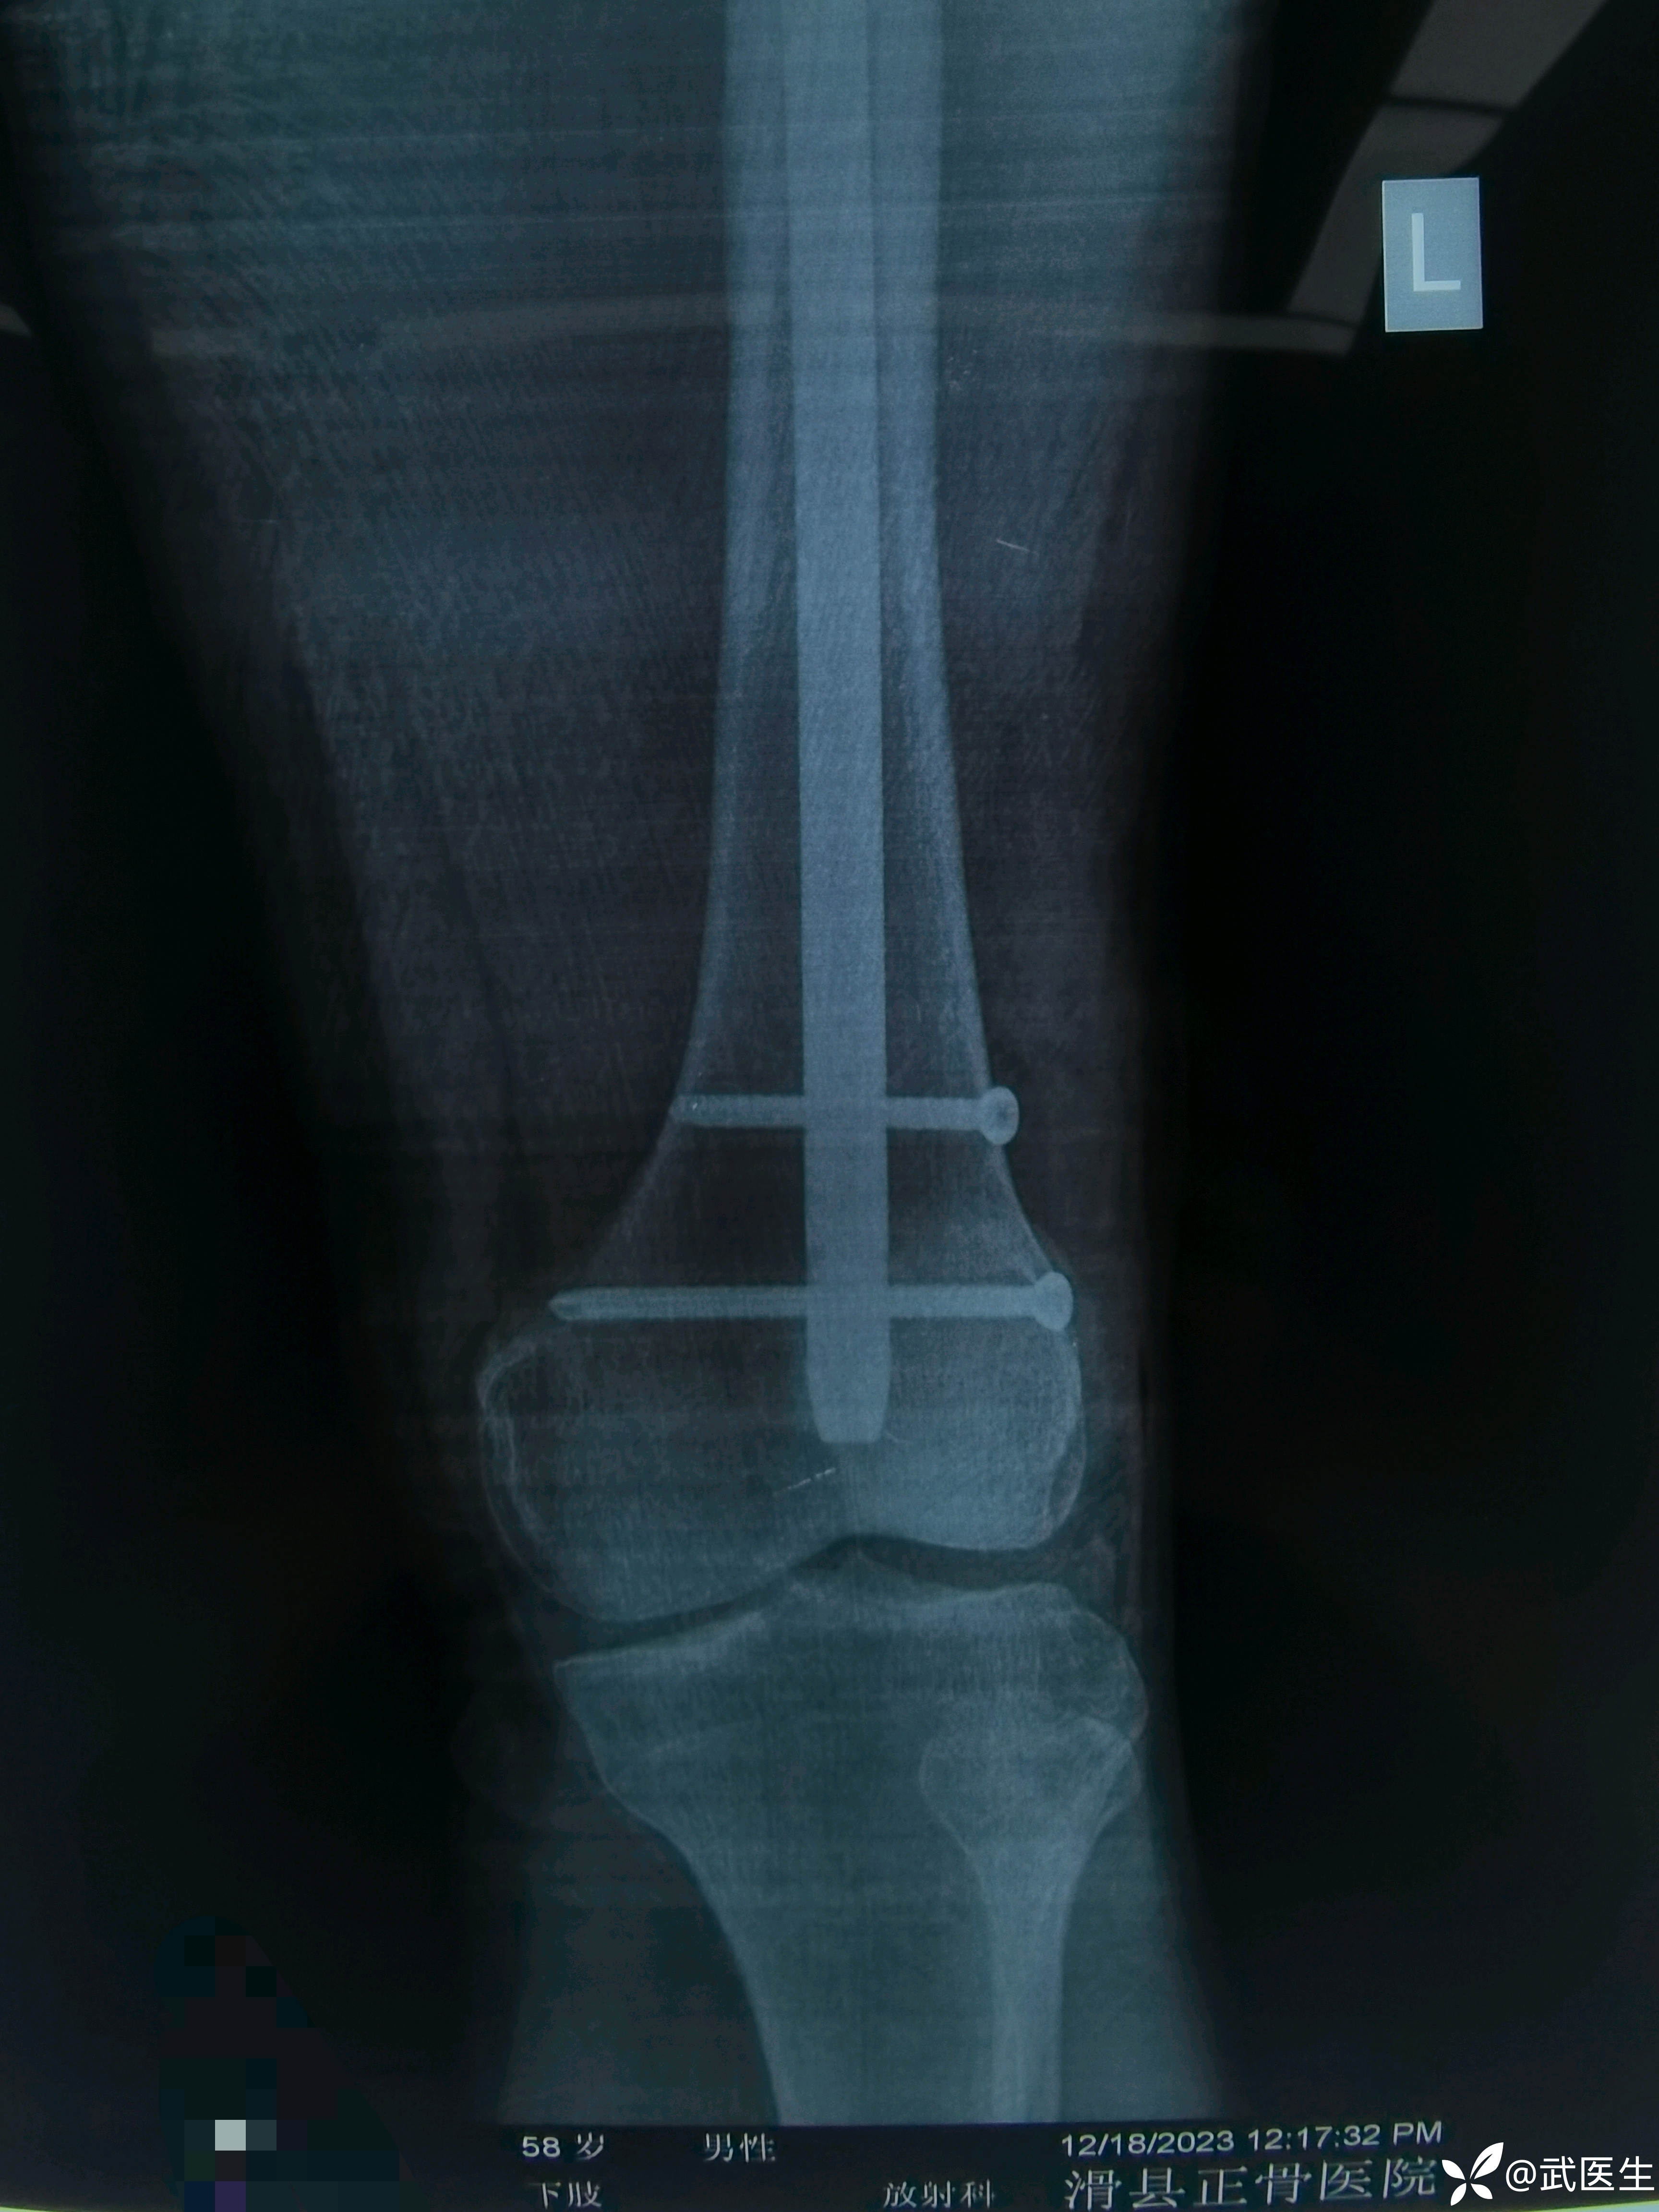

男,58岁,路滑摔倒致左髋疼痛活动受限一小时就诊,片子如下